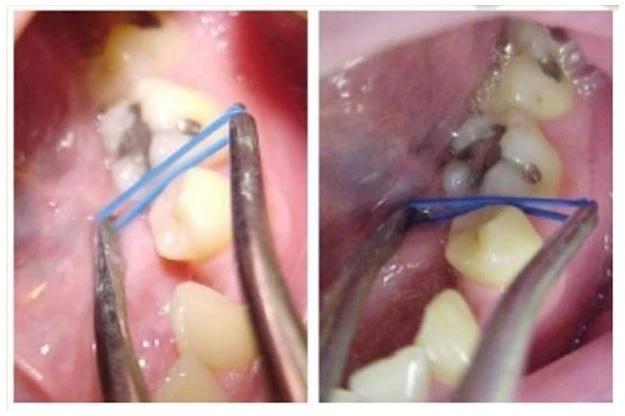

1.2. Lò xo Ni-ti

Lò xo Ni-ti dễ đặt vào mọi điểm tiếp xúc, giải phóng lực nhẹ, tự đứng tại chỗ và không cản trở khớp cắn, Lò xo đắt tiền hơn, tuy nhiên bạn có thể hấp và tái sử dụng, giảm chi phí xuống một nửa mỗi lần bạn đặt thêm.

Lò xo Ni-ti có thể mở đủ khoảng tiếp xúc để di chuyển sâu hơn về phía mô mềm. Phải chắc chắn luôn luôn đếm lò xo khi lấy bỏ nó. Bất cứ khi nào không thấy đủ thì phải tìm ở dưới mô lợi.

Chân đứng của lò xo có thể in dấu trên mô lợi trong trường hợp mô lợi này có thân răng lâm sàng ngắn. Có thể cắt ngắn chân lò xo Niti được bằng kìm cắt pin/ligature. Luôn kiểm tra để chắc chắn chân đứng của lò xo nằm ôm lấy cấu trúc răng và không kẹp vào mô lợi.